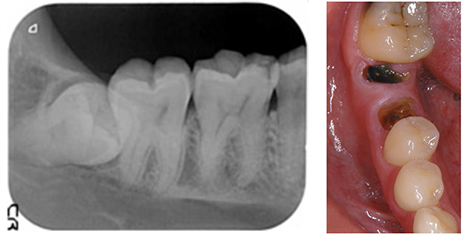

過去に抜いてインプラントにした方が良いと言われ 心配で当院を受診された35歳男性

BEFORE

向かって左端で横を向いてはえているのが親知らずを、抜歯せざるを得ない状態の放置された虫歯に移植します。

AFTER

治療後5年のレントゲンとそのカラー写真です。 この方の反対側の顎の中に埋もれている親知らずを抜歯し、即時移植で治療することができました。